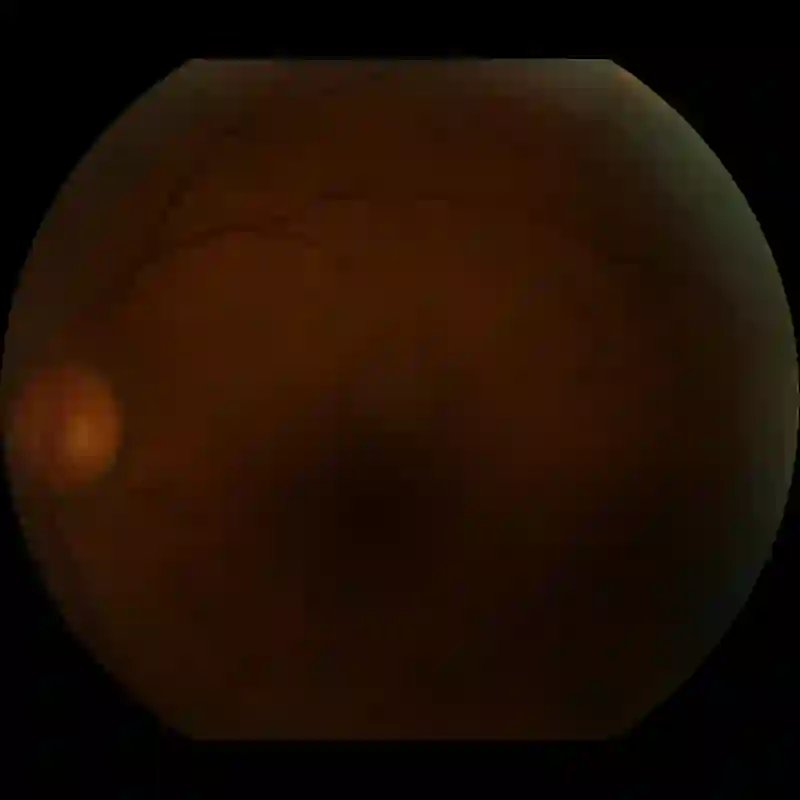

Clinical screening with low-quality fundus images is challenging and significantly leads to misdiagnosis. This paper addresses the issue of improving the retinal image quality and vessel segmentation through retinal image restoration. More specifically, a cycle-consistent generative adversarial network (CycleGAN) with a convolution block attention module (CBAM) is used for retinal image restoration. A modified UNet is used for retinal vessel segmentation for the restored retinal images (CBAM-UNet). The proposed model consists of two generators and two discriminators. Generators translate images from one domain to another, i.e., from low to high quality and vice versa. Discriminators classify generated and original images. The retinal vessel segmentation model uses downsampling, bottlenecking, and upsampling layers to generate segmented images. The CBAM has been used to enhance the feature extraction of these models. The proposed method does not require paired image datasets, which are challenging to produce. Instead, it uses unpaired data that consists of low- and high-quality fundus images retrieved from publicly available datasets. The restoration performance of the proposed method was evaluated using full-reference evaluation metrics, e.g., peak signal-to-noise ratio (PSNR) and structural similarity index measure (SSIM). The retinal vessel segmentation performance was compared with the ground-truth fundus images. The proposed method can significantly reduce the degradation effects caused by out-of-focus blurring, color distortion, low, high, and uneven illumination. Experimental results show the effectiveness of the proposed method for retinal image restoration and vessel segmentation.